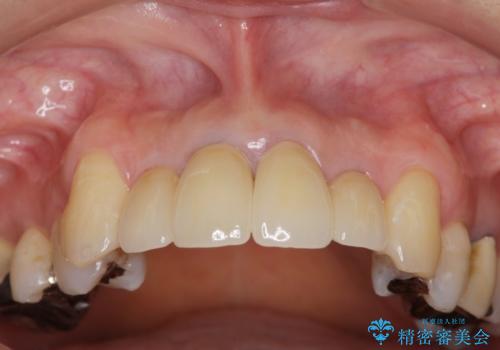

- クラウン周りの黒ずみが気になり、審美性の改善を求めて来院されました。

歯ぐきの位置は経年的に変化することがあります。その際にもジルコニアクラウンはクラウンの際が黒くなく目立ちにくく審美的なクラウンと言えます。